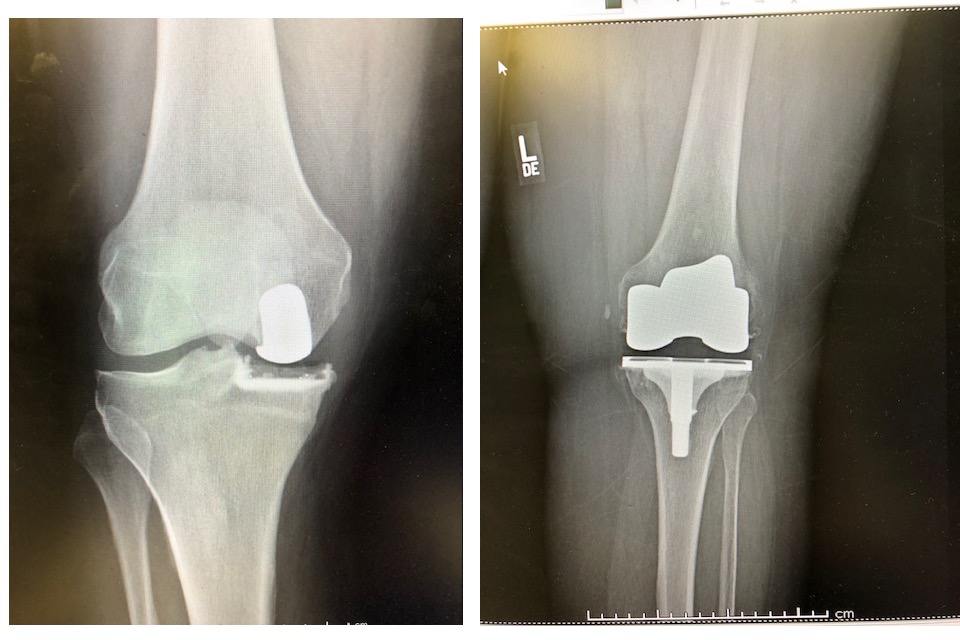

Total knee vs MIPKR